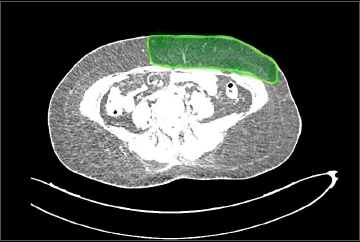

All patients underwent pre-operative volumetric analysis using both CT Angiography and 3D scanner. Post-operatively reconstructed breast volumes were measured using 3D scanner between 3-6 months. Breast volume on CT was measured by manually selecting the breast contour (Region of Interest, ROI) on each axial slice (Fig. 1). These ROIs were stacked to create a 3D reconstruction of the breast (Fig. 2). Hemiabdomen volume was measured on CTA from the anterior axillary line on the side of flap harvest, extending contralaterally up to the medial extent of the dominant perforator. This ROI corresponded to the anticipated DIEP flap territory based on perforator location and vascular dominance. Volume was then automatically calculated using Syringo.via software based on the cumulative ROI data(Fig. 3).

Figure 1. Breast volume on CT measured by manually selecting the breast contour (Region of Interest, ROI) on each axial slice.